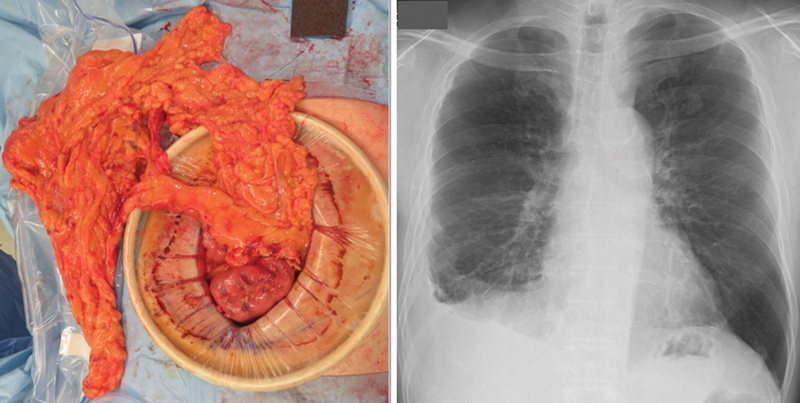

Background  No consensus exists regarding surgical intervention for rheumatoid nodule-related pneumothorax. Clinical policy decisions rely on individual clinicians' experience and are usually intractable. Case Description  A 50-year-old man with a difficult-to-treat rheumatoid arthritis-related pneumothorax was successfully treated with pedicle omentoplasty without recurrence at approximately 2 years posttreatment. To the best of our knowledge, this is the first report of a patient where pneumothorax did not recur due to firm adhesions despite fluctuating postoperative rheumatoid nodules, as captured by regular computed tomography imaging follow-ups. Conclusion  Pedicled omentoplasty is effective for rheumatoid nodule-related pneumothorax as it reduces pneumothorax recurrence.